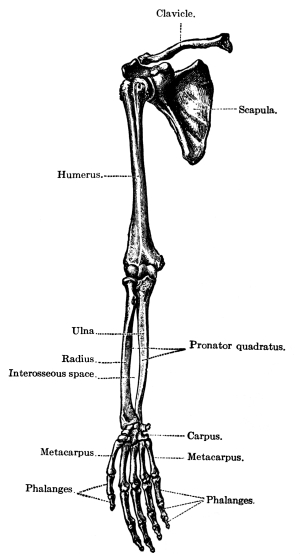

| The Upper Extremities | 171 |

The Shoulder Girdle, 171—The Clavicle, 171—The Scapula, 173—Shoulder Muscles, 174—The Humerus, 175—Upper Arm Muscles, 176—The Ulna, 177—The Radius, 178—The Wrist, 180—The Hand, 181—Meta-carpals, 181—Phalanges, 181—Muscles of the Forearm, 182—Muscles of the Hand, 184—Joints of the Upper Extremity, 185—Blood Supply of the Upper Extremity, 185—Nerves of the Upper Extremity, 186. |